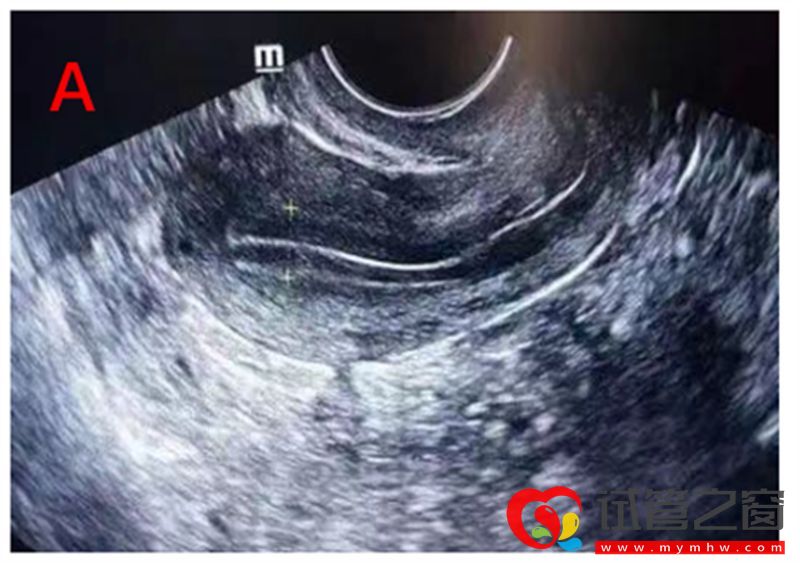

卵泡早期的内膜较薄,厚度约3~6 mm,随着卵泡生长,雌激素水平逐渐升高,内膜不断增厚。当卵泡达到成熟时,内膜厚度一般可达10-14mm。我们利用阴道超声根据Gonen分型标准,对内膜形态进行分型,分为三型:A、B、C型。A型及B型子宫内膜的妊娠率显著高于C型。

A型即三线型内膜,外层和中央为强回声线,外层和宫腔中线间为低回声区。常见于子宫内膜增生期。